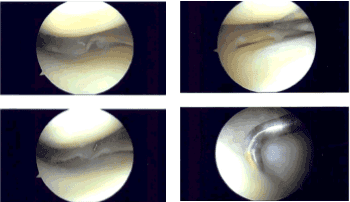

Imágenes de artroscopia intraoperatoria

El portal anterior medial se realizó mediante el uso de una aguja espinal y un cuchillo. El examen del compartimento femoral medial mostró desgarros horizontales y oblicuos del margen libre lateral a lo largo del cuerpo del homor posterior. Esto se hacía usando mordedores rectos y afeitadores.

Se podrían lograr márgenes equilibrados. El examen del resto del compartimento tibiofemoral fue bueno. El examen de la muesca infrapatela mostró un LCA intacto. El examen del compartimento tibial lateral mostró menisco intacto.

Hubo una lesión medial de grado III en el cartílago articular, que fue desbridada hasta obtener márgenes equilibrados. El hueso quedó entonces expuesto. El examen del compartimento patelofemoral mostró cartílago intacto. Se tomaron y guardaron las fotos finales.